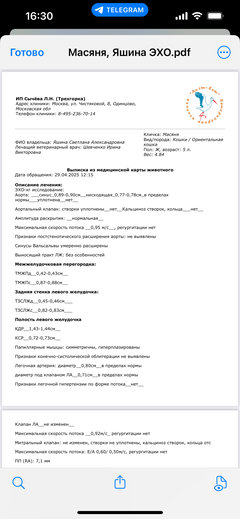

Забрали. Оказалось, что у малышки постоянно болит спина...

Ярко выраженная болезненность в области крестца, на обезболе полегче. По результатам приема невролога проведена миелография - множественная компрессия, возможно опухоль, возможно грыжа, нужно удалять...